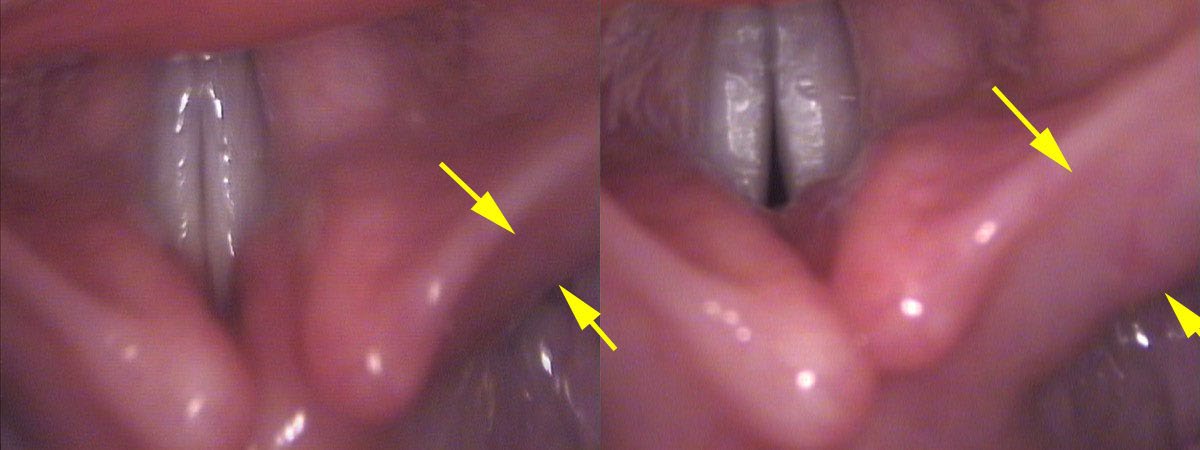

I record video of Maria’s vocal cords at the pitches where she is struggling, noting that the back of the vocal cords are not together. Actually, when I slow the recording down, I see the vocal cords come together initially and then pull slightly apart as actual sound production begins. The LCA muscle brings her vocal cords together, but moments later she tightens her PCA muscle and this pulls the vocal cords slightly apart at the rear. At very slow speeds, I can show Maria this muscle bulging as it contracts.

When the vocal cords are held apart, air leaks between them. By asking Maria to sing at her softest pitch, the air preferentially leaks out through the gap, as a whisper, rather than starting up the vocal cord vibrations that we would hear as a note. The posterior gap between the vocal cords is variable depending on her effort and thus the vocal impairment is variable. That is why her voice starts cutting out on different pitches each time we test her singing up the scale.